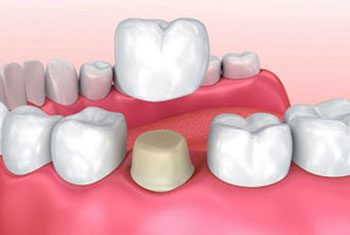

Zirconia Crowns:

For durable and aesthetically pleasing dental restorations, werecommend Zirconia Crowns, a type of tooth restoration treatment that covers severe decay and bad discoloration. Zirconia is a strong and biocompatible material that closely resembles the natural appearance of teeth. Our dental experts craft zirconia crowns with precision and artistry, ensuring a perfect fit and a seamless blend with your existing teeth. With zirconia crowns, you can achieve strong teeth and a pleasant smile.